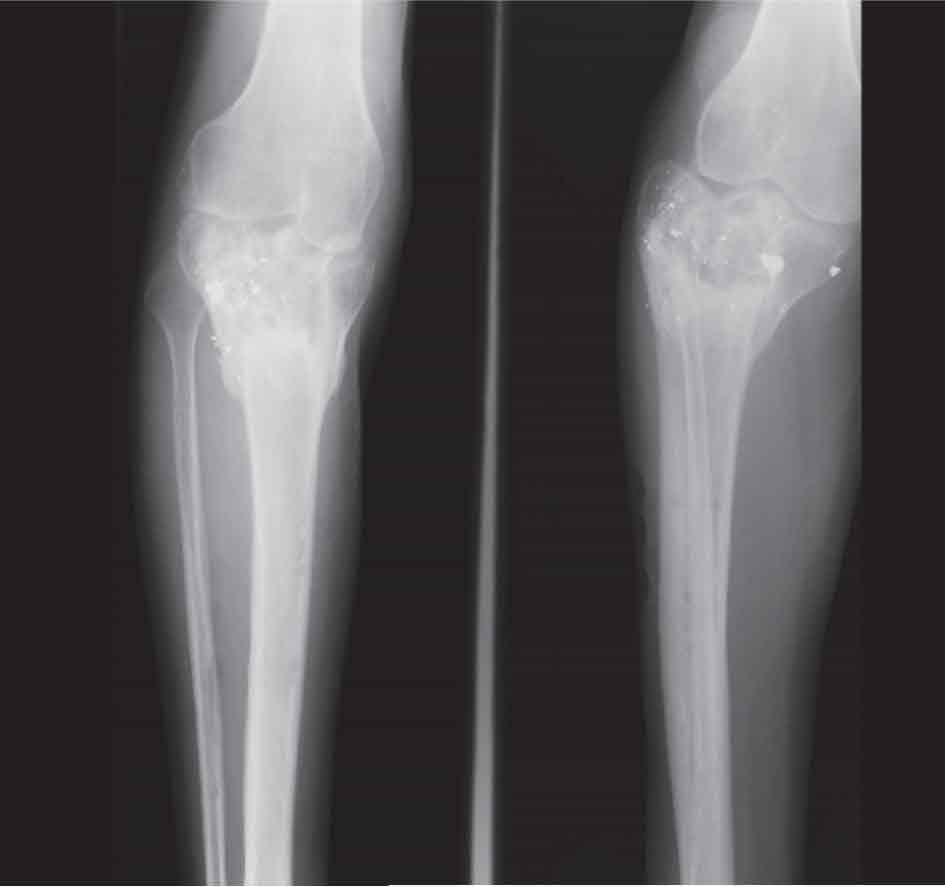

الدراسة الشعاعية: (الشكل 6) تظهر الصورة البسيطة الكسر وتساعد على التصنيف، ويستطب إجراء التصوير المقطعي المحوسب مع إعادة تركيب الكسر، وهو يظهر مدى تفتت الكسر ودرجة تبدله ويساعد على التخطيط للعمل الجراحي.

الشكل (6) أ- صورة بسيطة لكسر درجة ثانية، ب-ج تصوير طبقي محوري يظهر درجة التبدل وشدته مما يساعد على التخطيط للعمل الجراحي، د- صورة بسيطة بعد الاستجدال الجراحي.

ب- تشوه محور الطرف: الرَّوَح أو الفحج اللذان يحدثان نتيجة عدم الرد الجيد، أو نتيجة عدم الرد البدئي (الشكل10).

الشكل (10): المضاعفات، كسر درجة 6 معقد- طلق ناري- عولج علاجاً محافظاً، واندمل الكسر اندمالاً معيبا